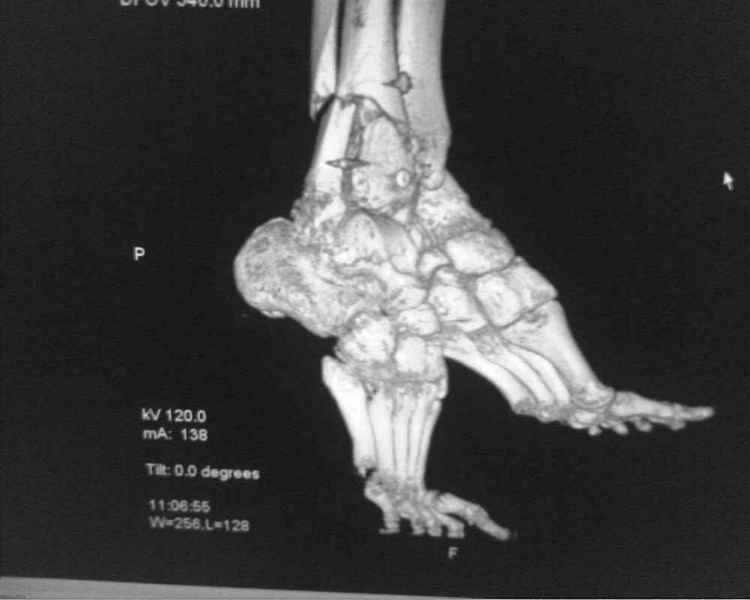

[Ortho] [1/2] Метатарзал краш синдром в порочном сращении (эквинусная стопа), несращение сегментарного перелома костей голени после БИОС , ПТФБ, ХВН СЕАР С-6.

Больной 39 лет. Травма получена в ДТП 21.09.09г. был госпитализирован в обл. больницу

соседней области с диагнозом сочетанная травма зчмт сотрясение головного мозга

сегментарный перелом костей правой голени с\3-н\3, суральный флеботромбоз циркулярные

некрозы н\3 правой голени правого голеностопного сустава лечение скелетным вытяжением за

пяточную кость. переведён в наше отделение 6.10.09г. возобновлено скелетное вытяжение,

перевязки, иссечение некрозов, антикоагулянты. На уздг диагноз флеботромбоза

подтвержден. 28.10.09 операция БИОС правой б\берцовой кости штифтом PTNL остеомед .

остеосинтез м\берцовой кости не выполняли из-за наличия гранулирующих ран и некрозов в

месте операционного доступа. Вторым этапом планировалось наложить аппарат Илизарова для

выведения стопы из эквинуса и динамизации штифта. Но из-за наличия гранулирующих ран и

некрозов в местах проведения спиц на стопе и голени 19.11.09 переведен в ожоговое отделение

для САДП гранулирующих ран после некрозов. 23.11.09 САДП. В послеоперационном периоде-

длительное заживление ран с лизисом кожных лоскутов, манифестное развитие ХВН с

формированием трофических язв и лимфэдемы. Больной явился на госпитализацию 13.01.10г.

локальный статус и свежие снимки прилагаю. Данные уздг выложу позже. Что в этой ситуации

делать я не знаю. Признаков сращения на Rg-нет плюс метафизарный фрагмент кивнул на вальгус.